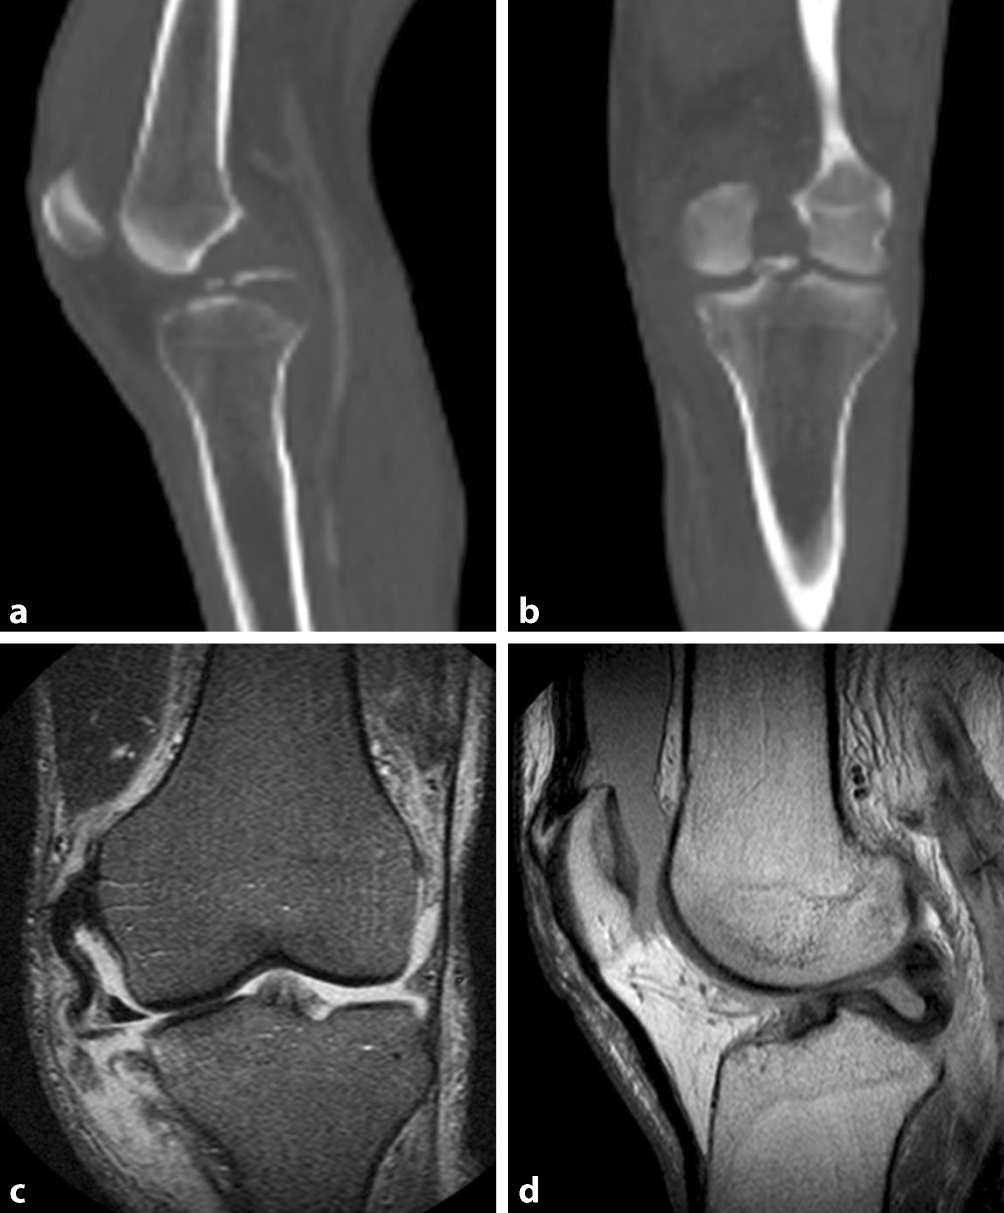

Abb. 3

CT (a, b) und MRT (c, d) eines nach medial luxierten Risses des Außenmeniskus sowie knöchernen Ausrisses des hinteren Kreuzbandes. Fallbeschreibung: 60-jähriger Mann mit Kniegelenkluxation nach Fahrradsturz. In dem CT zeigte sich ein knöcherner Ausriss des hinteren Kreuzbandes (a und b), die angiographische Phase zeigte keine Gefäßbeteiligung. In der zusätzlich präoperativ angefertigten MRT-Untersuchung war der knöcherne Ausriss des hinteren Kreuzbandes nur schlecht zu erkennen (d). Allerdings lässt sich ein nach medial luxierter Riss des Außenmeniskus (d), eine Ruptur des medialen Kollateralbandes nachweisen (c) sowie der Verdacht auf eine Affektion des vorderen Kreuzbandes stellen

Bild vergrößern